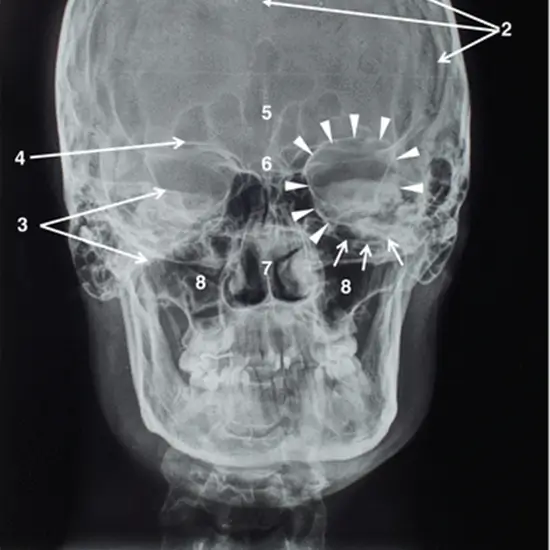

With an X-ray of the optic foramen test, the opening of the optic canal, called the optic foramen, at the base of the skull can be seen. The optic nerve and the ophthalmic artery go through the optic canal and into the orbital cavity.